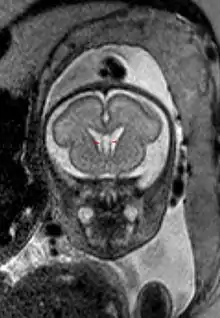

Полость прозрачной перегородки (лат. cavum septi pellucidi) — полость, находящаяся между листками прозрачной перегородки. Полость содержит ликвор, попадающий туда через поры в листках.[1]

Спереди полость ограничена коленом мозолистого тела; сверху — стволом мозолистого тела; сзади — передними ножками и столбами свода мозга; снизу — передней комиссурой и клювом мозолистого тела; латерально — листками прозрачной перегородки.[2]

Собственно полость прозрачной перегородки расположена на уровне основания передних рогов боковых желудочков мозга, а её распространение в заднем направлении в область тел боковых желудочков выделяют под названием полость Верге (лат. cavum vergae). Во время эмбрионального развития происходит закрытие полостей в задне-переднем направлении, из-за чего персистирование полости Верге при закрытой полости прозрачной перегородки встречается значительно реже.